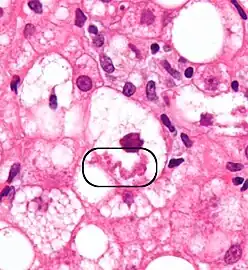

The primary characteristic of MASLD is the accumulation of lipids in the liver, largely in the form of triglycerides.[19] However, the mechanisms by which triglycerides accumulate and the reasons that accumulation can lead to liver dysfunction are complex and incompletely understood.[19][47][48] MASLD can include steatosis along with varied signs of liver injury: either lobular or portal inflammation (a form of liver injury) or ballooning degeneration. Similarly, NASH can include histological features such as portal inflammation, polymorphonuclear cell infiltrates, Mallory bodies, apoptotic bodies, clear vacuolated nuclei, microvesicular steatosis, megamitochondria, and perisinusoidal fibrosis.[16] Hepatocyte death via apoptosis or necroptosis is increased in MASH compared with simple steatosis, and inflammation is a hallmark of MASH.[32]

NASH (inflammation) and fibrosis stage 1

NASH (inflammation) and fibrosis stage 2

Lobular inflammation